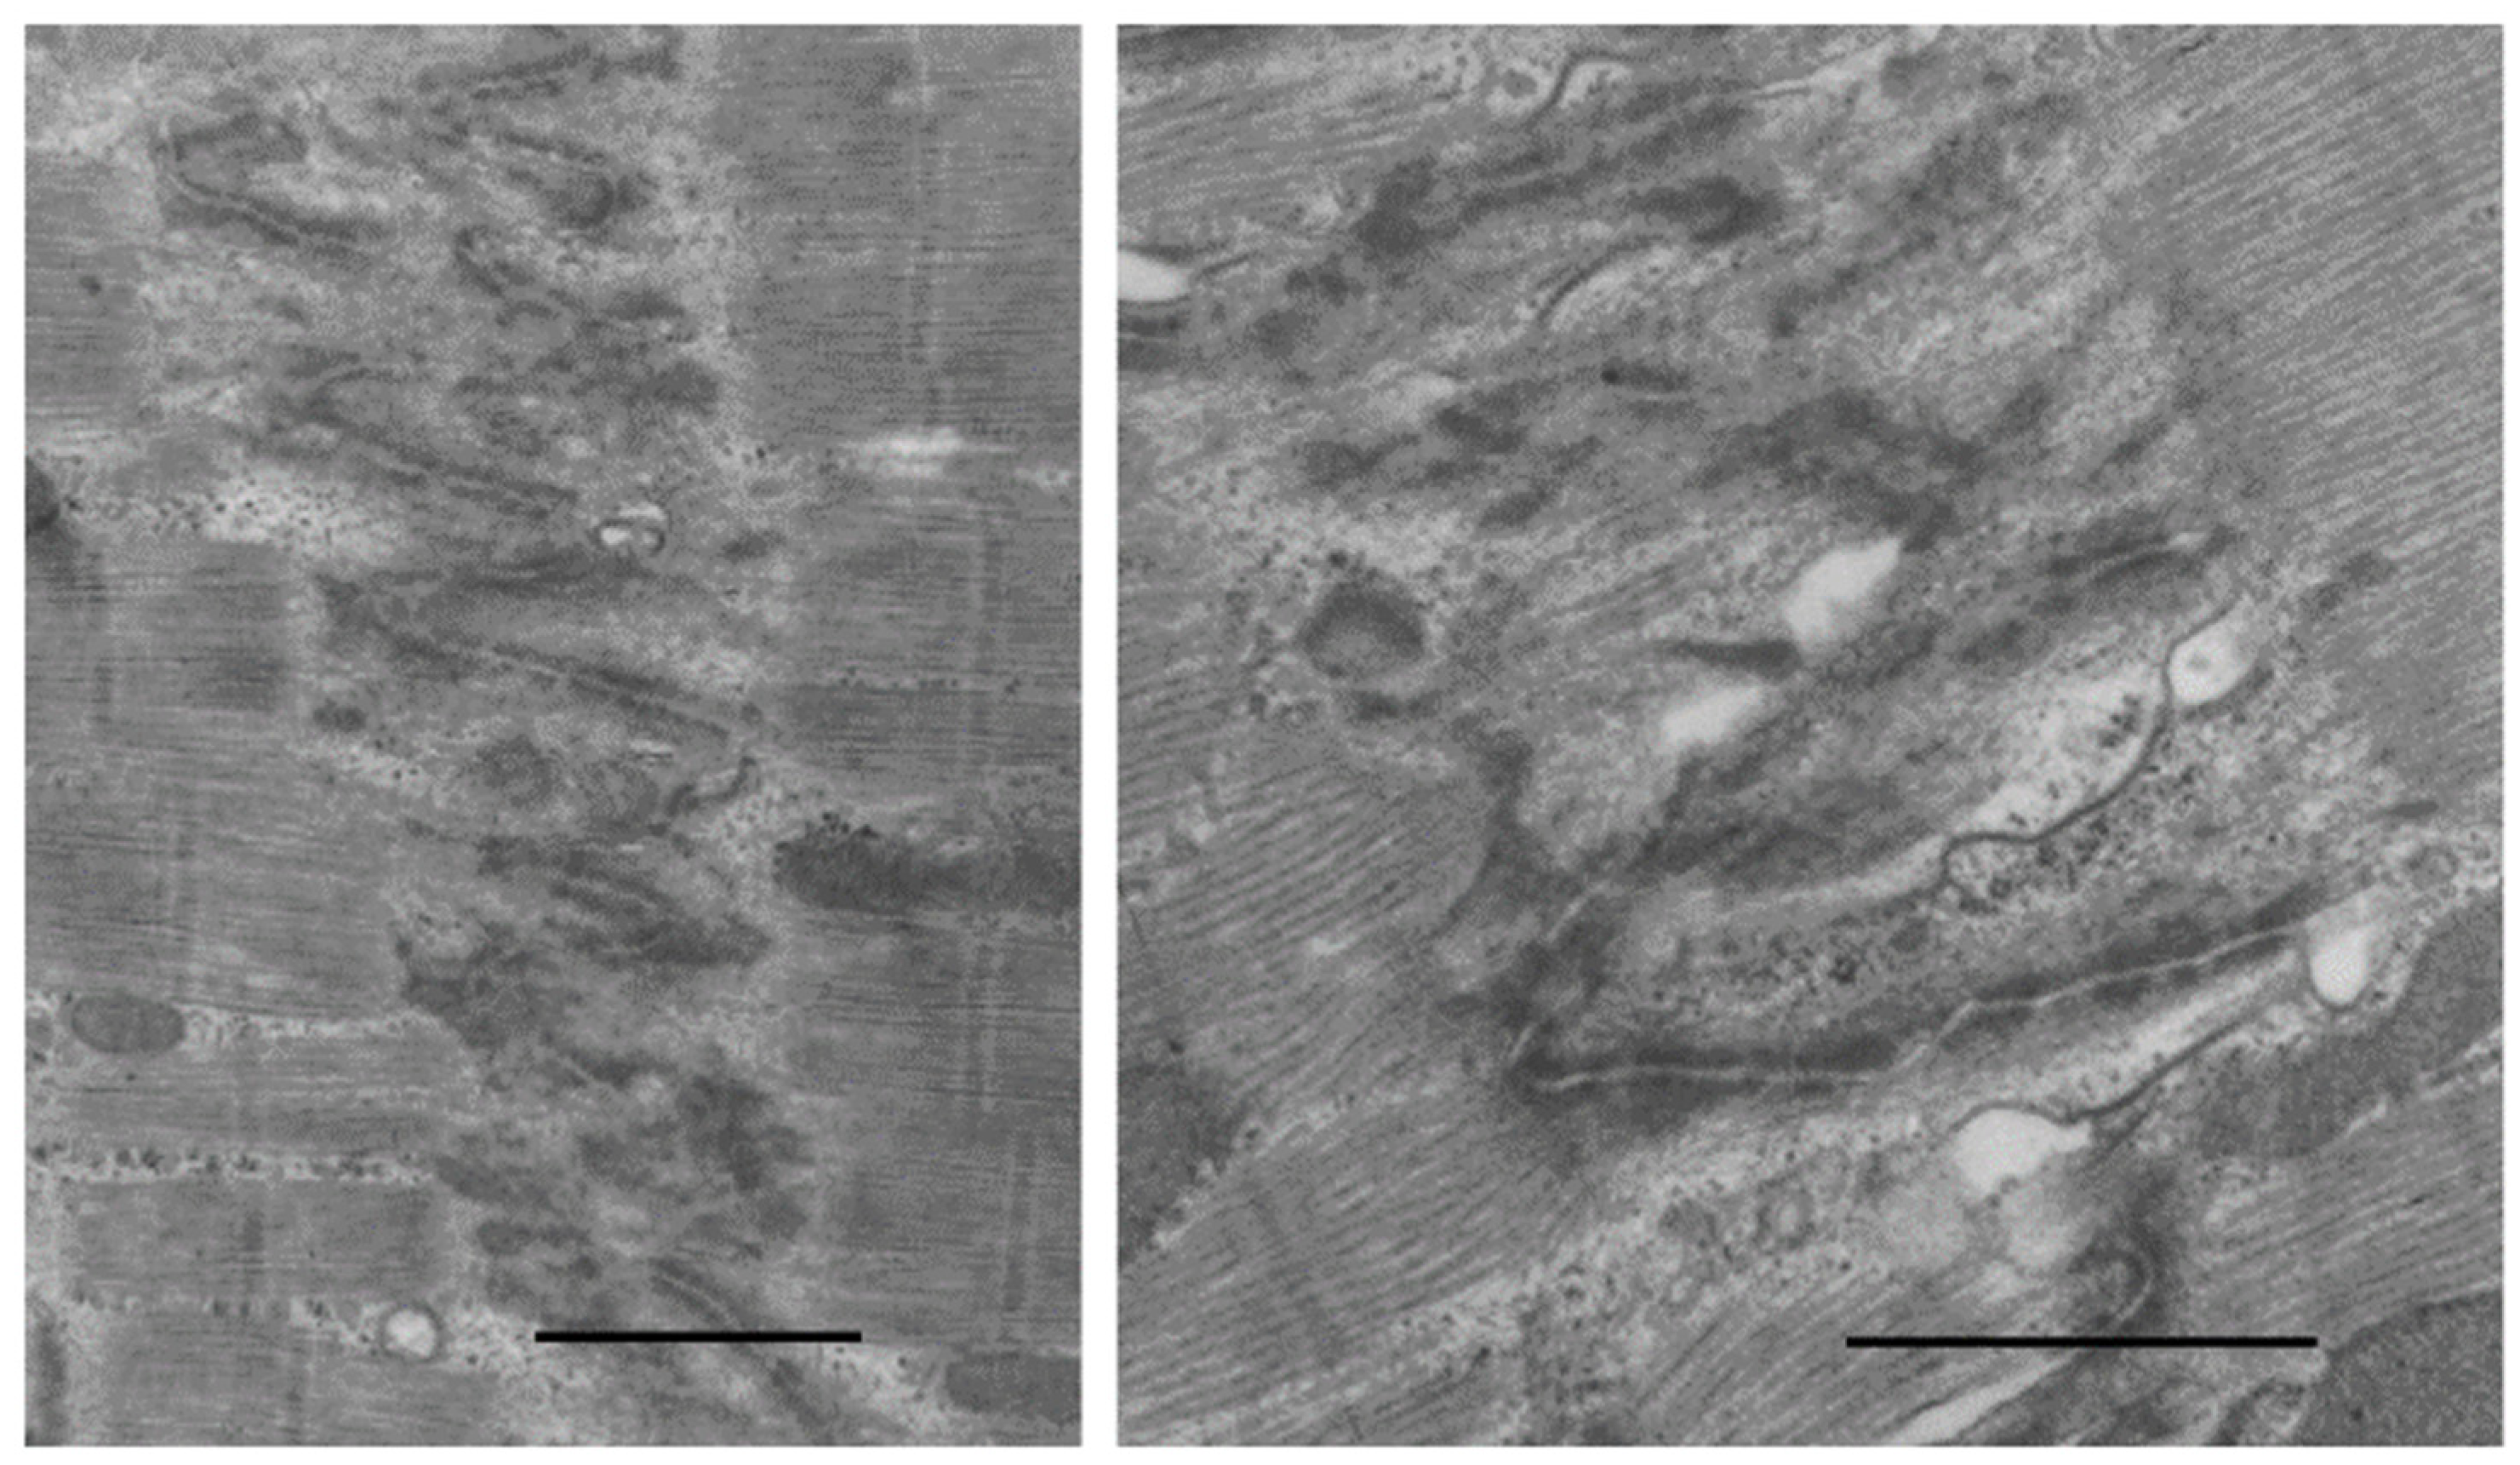

9.2. Mitochondrial Morphology in Hypertrophy and Failure

- Bishop, S.P.; Cole, C.R. Ultrastructural changes in the canine myocardium with right ventricular hypertrophy and congestive heart failure. Lab. Investig. 1969, 20, 219–229. [Google Scholar] [PubMed]